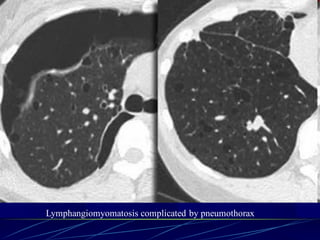

Langerhans cell histiocytosis

Lymphangiomyomatosis complicated by pneumothorax